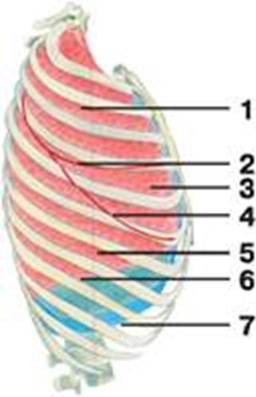

Анатомические изображения сегментов легких различных животных

Раздел: Другие животные